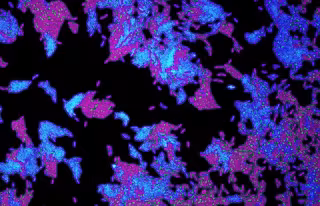

Archivo - Células de la bacteria patógena Pseudomonas aeruginosa utilizada en el estudio

Archivo - Células de la bacteria patógena Pseudomonas aeruginosa utilizada en el estudio - SEAN BOOTH - Archivo